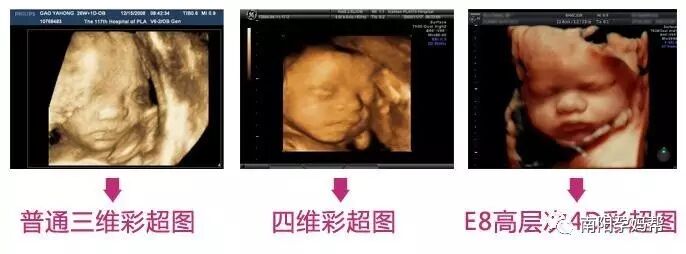

很多孕妈咪疑惑"听说GE-E8四维彩超跟普通的四维彩超差别很大, 可是不知道到底有哪些区别呢?" 下面我们就一起来看看吧!

(彩超清晰度对比图)

通过E8不仅能让孕妈可以看到宫内胎儿,如打哈欠、伸懒腰、吮手指等等奇妙的动作,还可以打印宫内高清写真,作为送给未来宝宝的珍贵礼物喔!